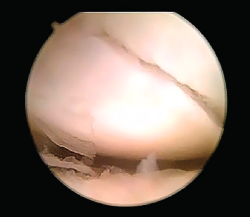

En cuanto al diagnóstico, la controversia reside en cuándo y qué pruebas complementarias realizar en las sospechas clínicas de fractura sin una imagen de radiología concluyente. A menudo las fracturas agudas pasan desapercibidas; la sensibilidad de la radiología va del 84 al 98%(1), la resonancia magnética nuclear (RMN) puede ser útil, con una sensibilidad superior al 95%, pero con una especificidad inferior(2), siendo la tomografía computarizada (TC) la más sensible y especifica(3)(Figura 1).

Figura 1. Imagen de fractura no desplazada de escafoides en tomografía computarizada.